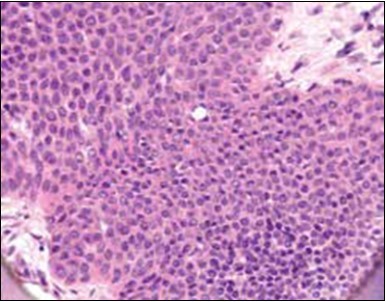

Classically, intra-epidermal and dermal nests of tumour cells exhibiting cellular atypia and enhanced mitotic activity are enunciated. Tumour aggregates articulate well demarcated, enlarged, atypical polygonal cells with indistinct cellular and nuclear outline, nuclear hyperchromasia , irregular nuclei, vesicular or prominent nucleoli and minimal eosinophilic cytoplasm. Polygonal tumour cells can depict central keratinisation 6, 7.

Granular arrangement of malignant cells and intercellular bridges are conspicuous with the demonstration of nuclear atypia, pleomorphism, prominent mitosis and tumour necrosis. A peripheral palisade is discernible within the cellular aggregates. Mitotic figures are common and can be quantified as up to 12 mitosis/ high power field. Tumour differentiation can prominently be of the ductal category with the demonstration of intra-cytoplasmic lumina. Comedo type tumour necrosis is evident along with foci of squamous differentiation The neoplasm is reactive to periodic acid Schiff ‘s (PAS) stain. (Figure 1, Figure 2, Figure 3, Figure 4, Figure 5, Figure 6, Figure 7, Figure 8, Figure 9, Figure 10, Figure 11, Figure 12, Figure 13.

Figure 1.Solid aggregates of tumour cells and duct structures in eccrine porocarcinoma (14).